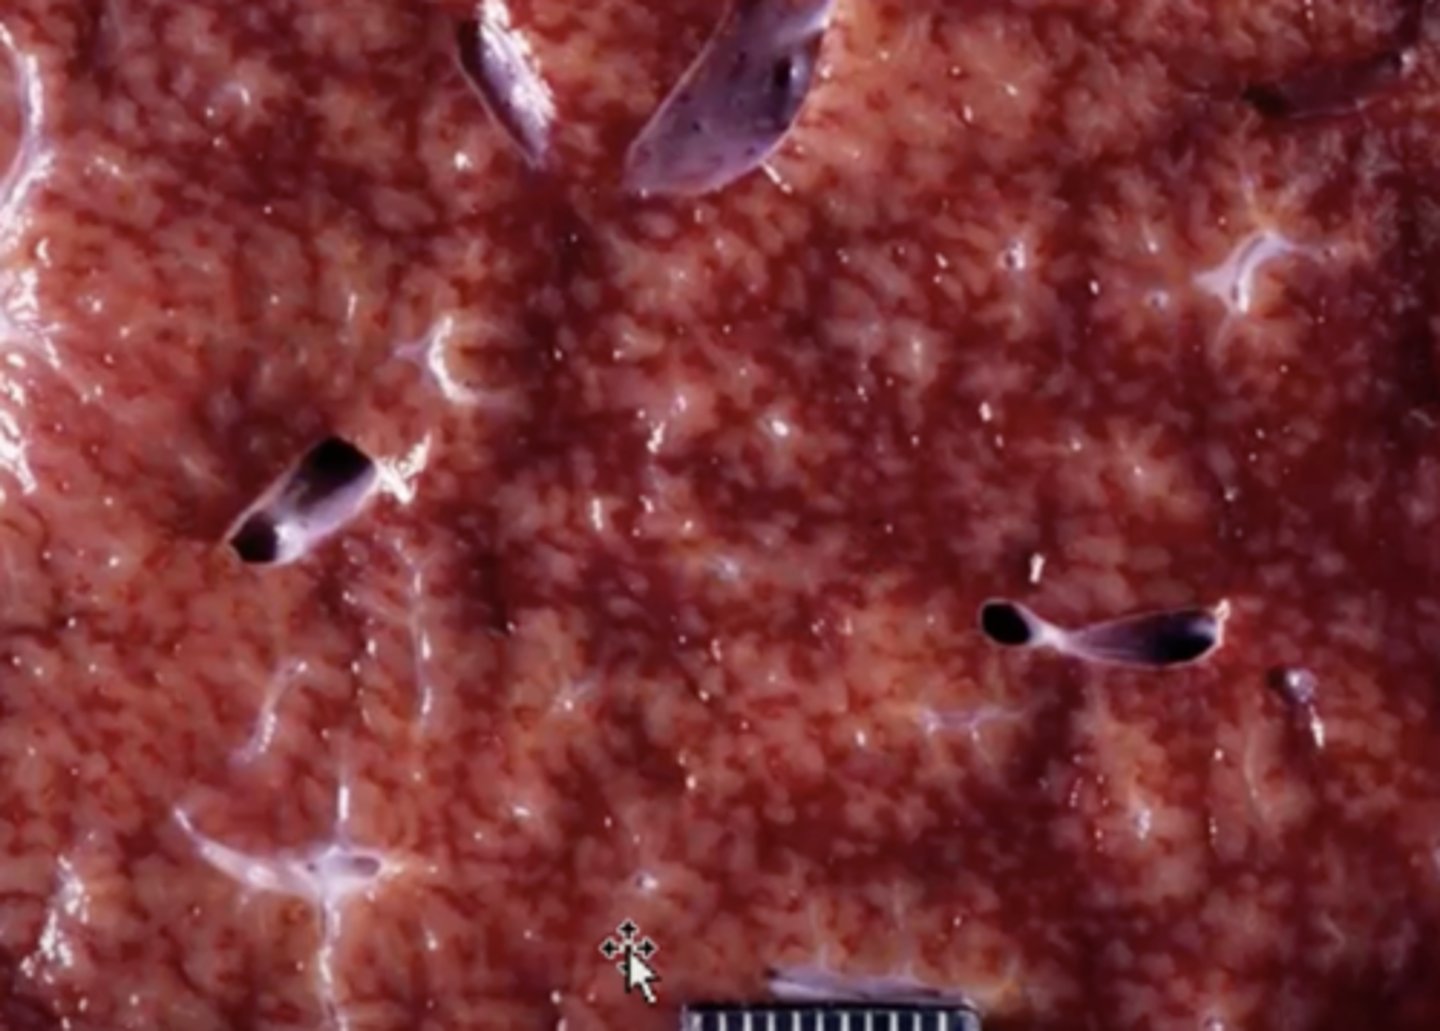

Parasite migration

-black lines indicate where parasites have migrated through

(hemorrhagic tracts)

- white spots/lines are scars from previous migrations

What has caused this gross appearance of this sheep liver?

Flukes!!

-migration of flukes through liver parenchyma

What caused this lesion in the liver of a deer?

Fascioloides magna migration

-black lines

-hepatocytes have filled with fat (white spots) due to hypoxia

-fibrous connective tissue from damage

What has caused this gross appearance of this liver?